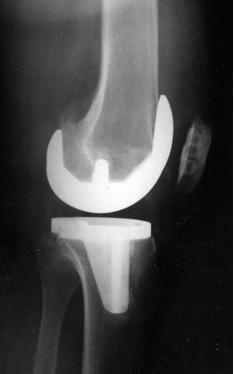

Больной получает антибиотики для снижения риска развития инфекции. Производится разрез для получения доступа к внутренним поверхностям сустава. Затем удаляются участки хряща и костной ткани с нижней поверхности бедренной кости и верхней поверхности большеберцовой кости. После этого производится имплантация искусственного сустава, сделанного обычно из металла и пластика (см. рис. 2).

Тип имплантата, метод операции и локализация разреза зависят от индивидуальных предпочтений пациента и хирурга, выполняющего операцию. Все протезы коленного сустава состоят из бедренного компонента, большеберцового и надколенникового компонентов. Существует множество вариантов протеза от разных производителей. Большинство из них служит не менее 10 лет. Искусственный сустав действует дольше у пожилых, менее физически активных пациентов и у больных ревматоидным артритом (по сравнению с больными остеоартритом).

После проведения имплантации производится контрольный рентгеновский снимок колена (см. рис. 3,4).

Он позволяет хирургу подтвердить и документировать правильное положение сустава и служит для сравнения с последующими снимками.

Полная замена коленного сустава это распространенная хирургическая процедура, которая может помочь в случаях, когда неоперативные методы лечения (использование наколенников или ортопедических стелек и медикаментозное лечение) не помогают. Операция включает в себя замену всех трех отделов коленного сустава (см. рис. 1) протезом с тем, чтобы уменьшить боль и улучшить функционирование сустава. Большинство кандидатов на операцию страдают от болей в суставе из за артрита. При подготовке к замене коленного сустава пациент должен пройти обследование, включающее опрос, физикальное обследование, рентген, лабораторные анализы, а также обсудить с врачом все выгоды и возможные осложнения операции и получить информацию об альтернативных методах лечения. Операция проводится под анестезией для временного обездвиживания и снятия боли. Хирург производит разрез для доступа к полости коленного сустава и затем удаляет часть хряща и костной ткани с нижней поверхности бедренной кости и верхней поверхности большеберцовой кости. Далее производится вживление искусственного сустава, сделанного из металла и пластмасс. После операции пациент получает лекарства для предотвращения инфекции и для обезболивания. Также принимаются меры для предотвращения тромбообразования – препараты разжижающие кровь и сдавливающие устройства для ног или эластичные чулки. Некоторым пациентам предложат использование устройства для продолжительного пассивного движения – механизм, который приподнимает и медленно движет прооперированную ногу. После операции необходимо работать в тесном контакте с физиотерапевтом для укрепления мышечной силы и возобновления нормального объема движений в коленном суставе. Пациент может вернуться к нормальной деятельности в течение трех – шести недель после операции , после завершения программы реабилитации, может заниматься видами спорта с небольшой нагрузкой на коленный сустав (ходьба, плавание, езда на велосипеде). Послеоперационные осложнения возникают редко и, в основном, могут быть предотвращены с помощью тщательного послеоперационного ухода.